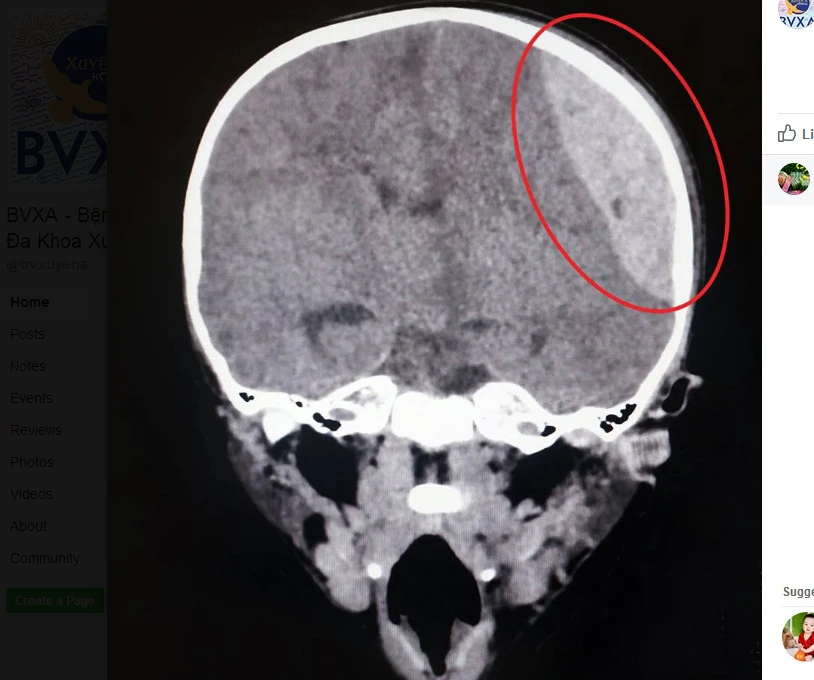

Kết quả chẩn đoán cho thấy bé K bị máu tụ ngoài màng cứng vùng thái dương trái, nứt xương sọ trán, cấu trúc đường giữa não lệch sang phải khoảng 9 mm.

Bé K bị nứt xương sọ trán. Ảnh: LÊ PHỤNG